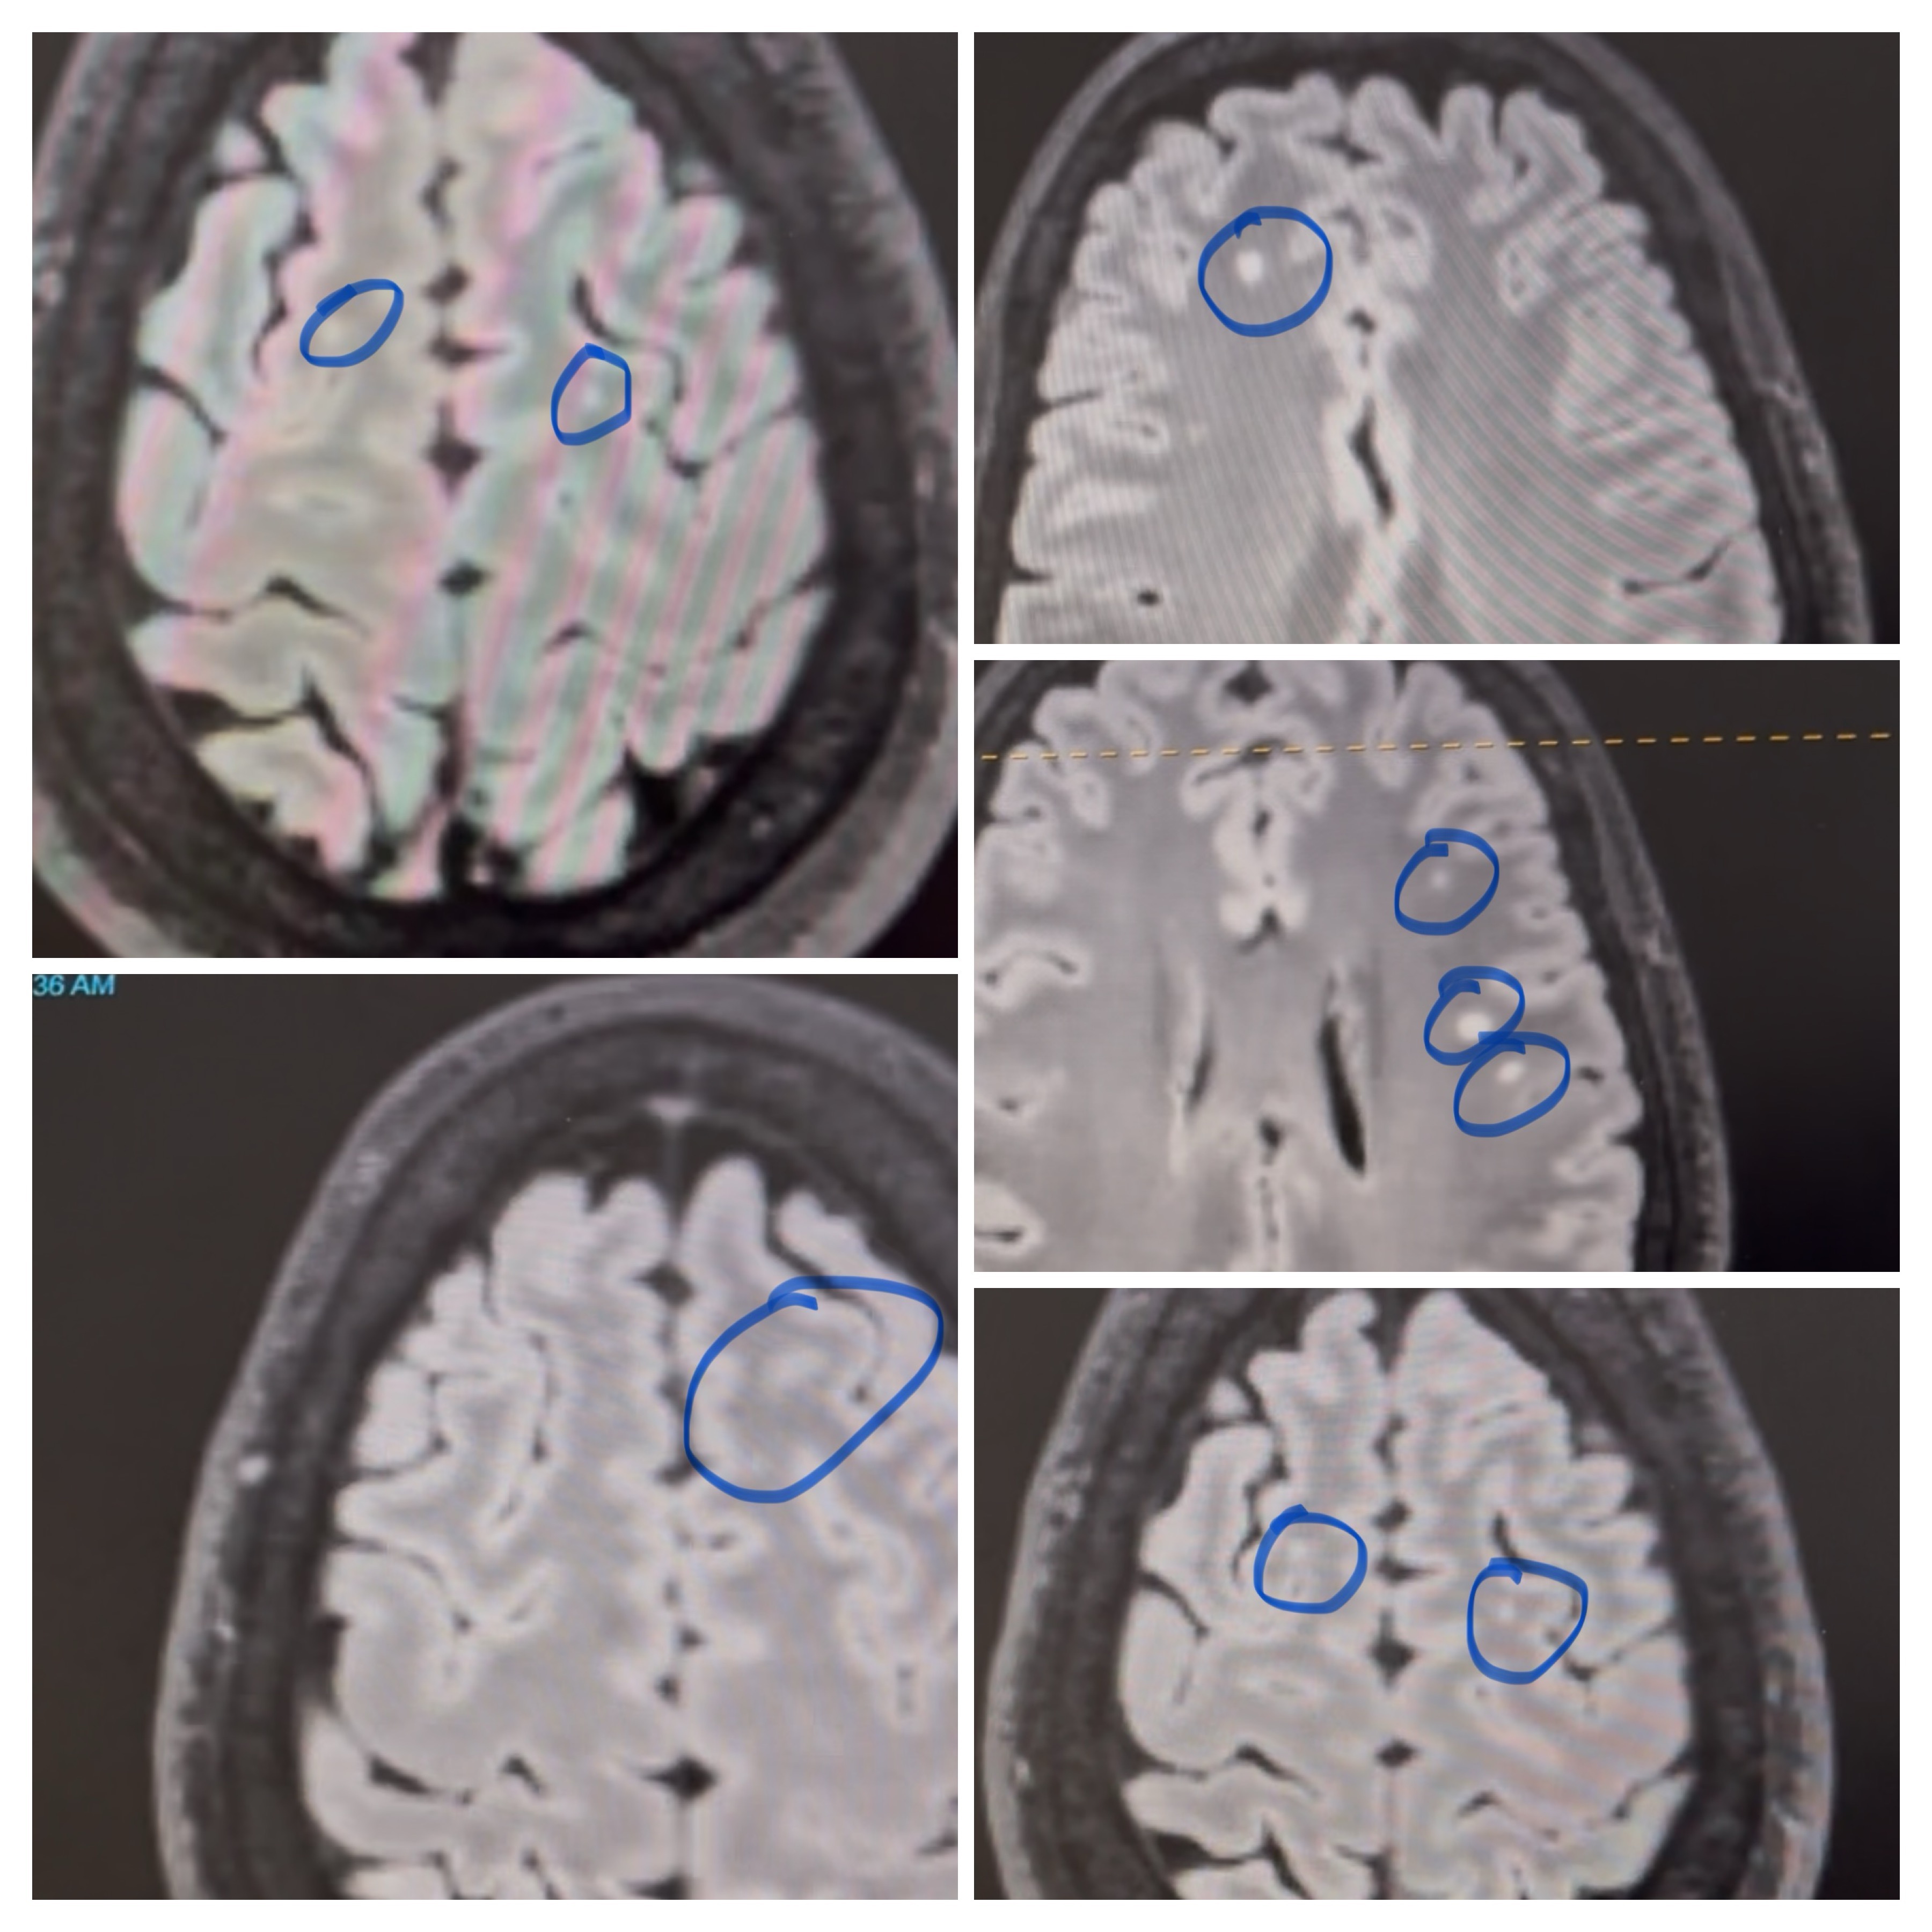

Diagnosed: demyelinating disease, nerve damage, neurological disorders, dental reconstruction, and jaw surgery.